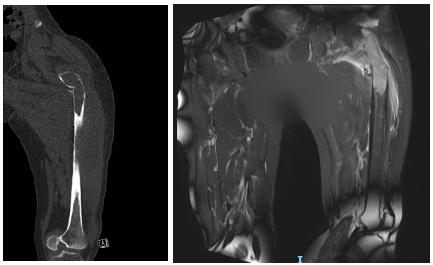

术前影像显示:患者左股骨中上段骨质破坏、病理骨折,骨折移位明显

经过术前充分的准备以及术中的精细操作,15cm长度的股骨上段肿瘤被完整切除,患者成功装上了髋关节肿瘤假体。术后一周,梁女士在医护人员的帮助下,通过积极的治疗和康复锻炼,已能在助行器的帮助下下地行走。